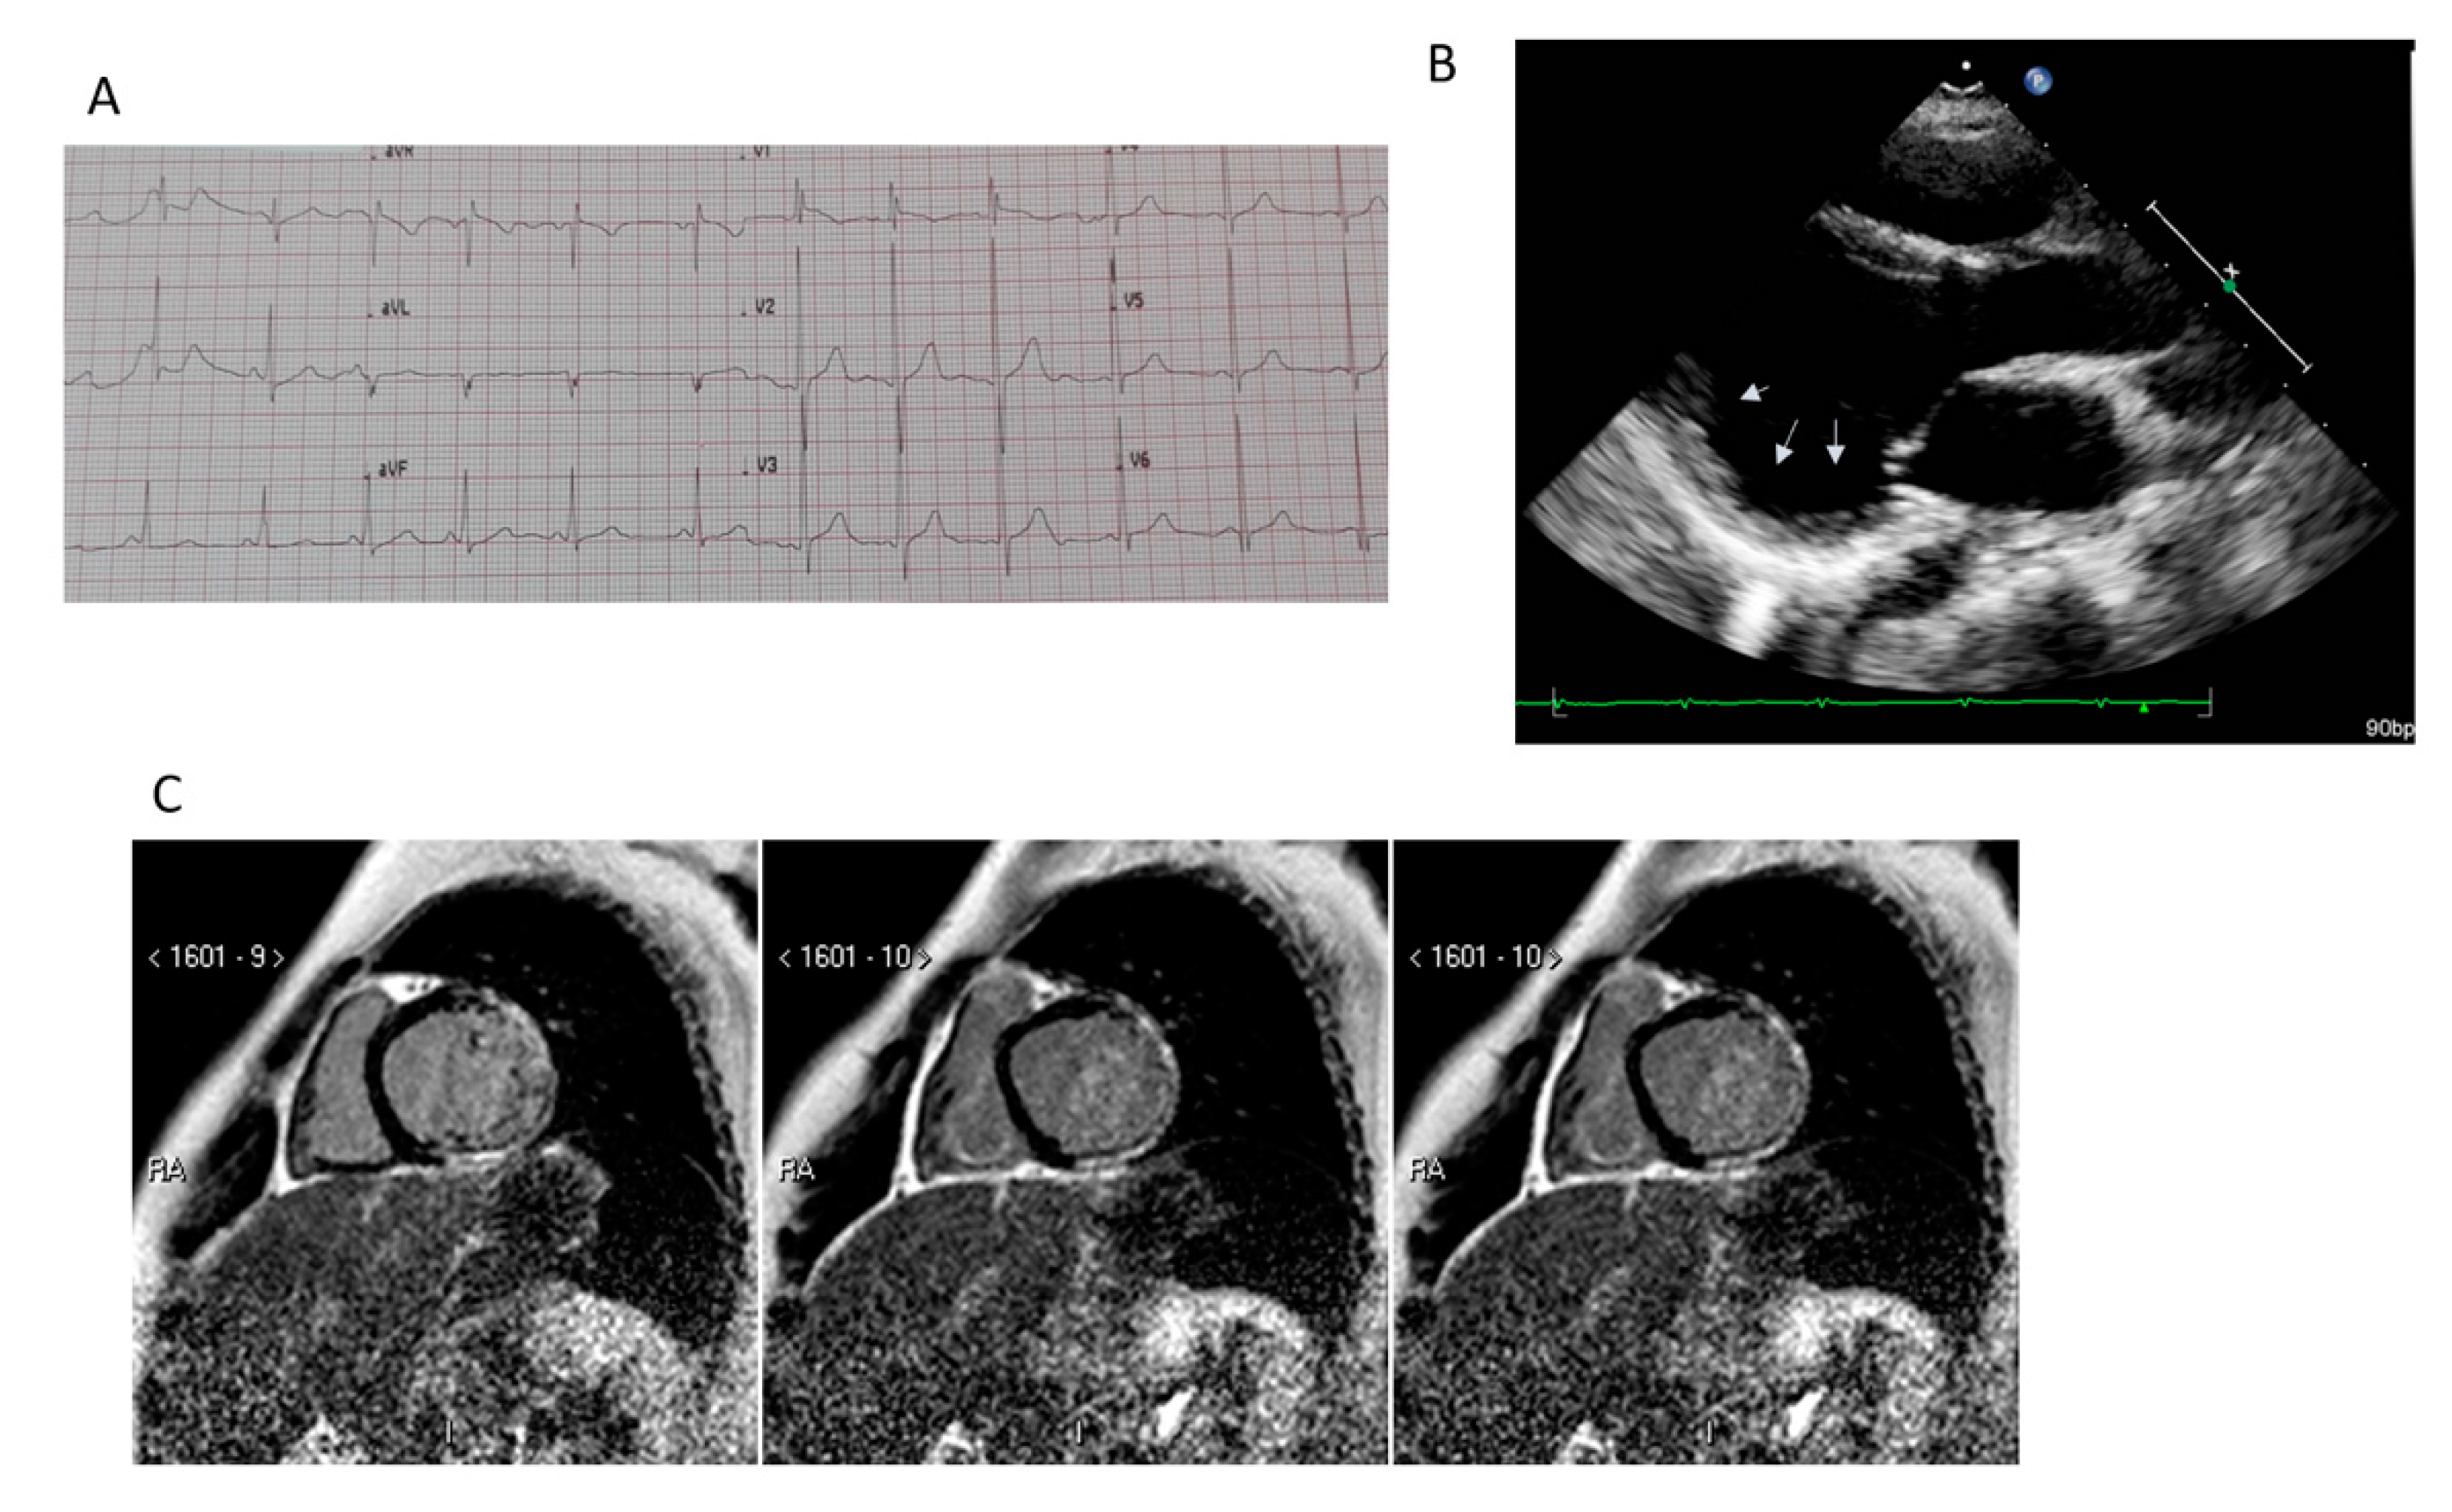

5.1. Transthoracic Echocardiography

5.2. Cardiac Magnetic Resonance